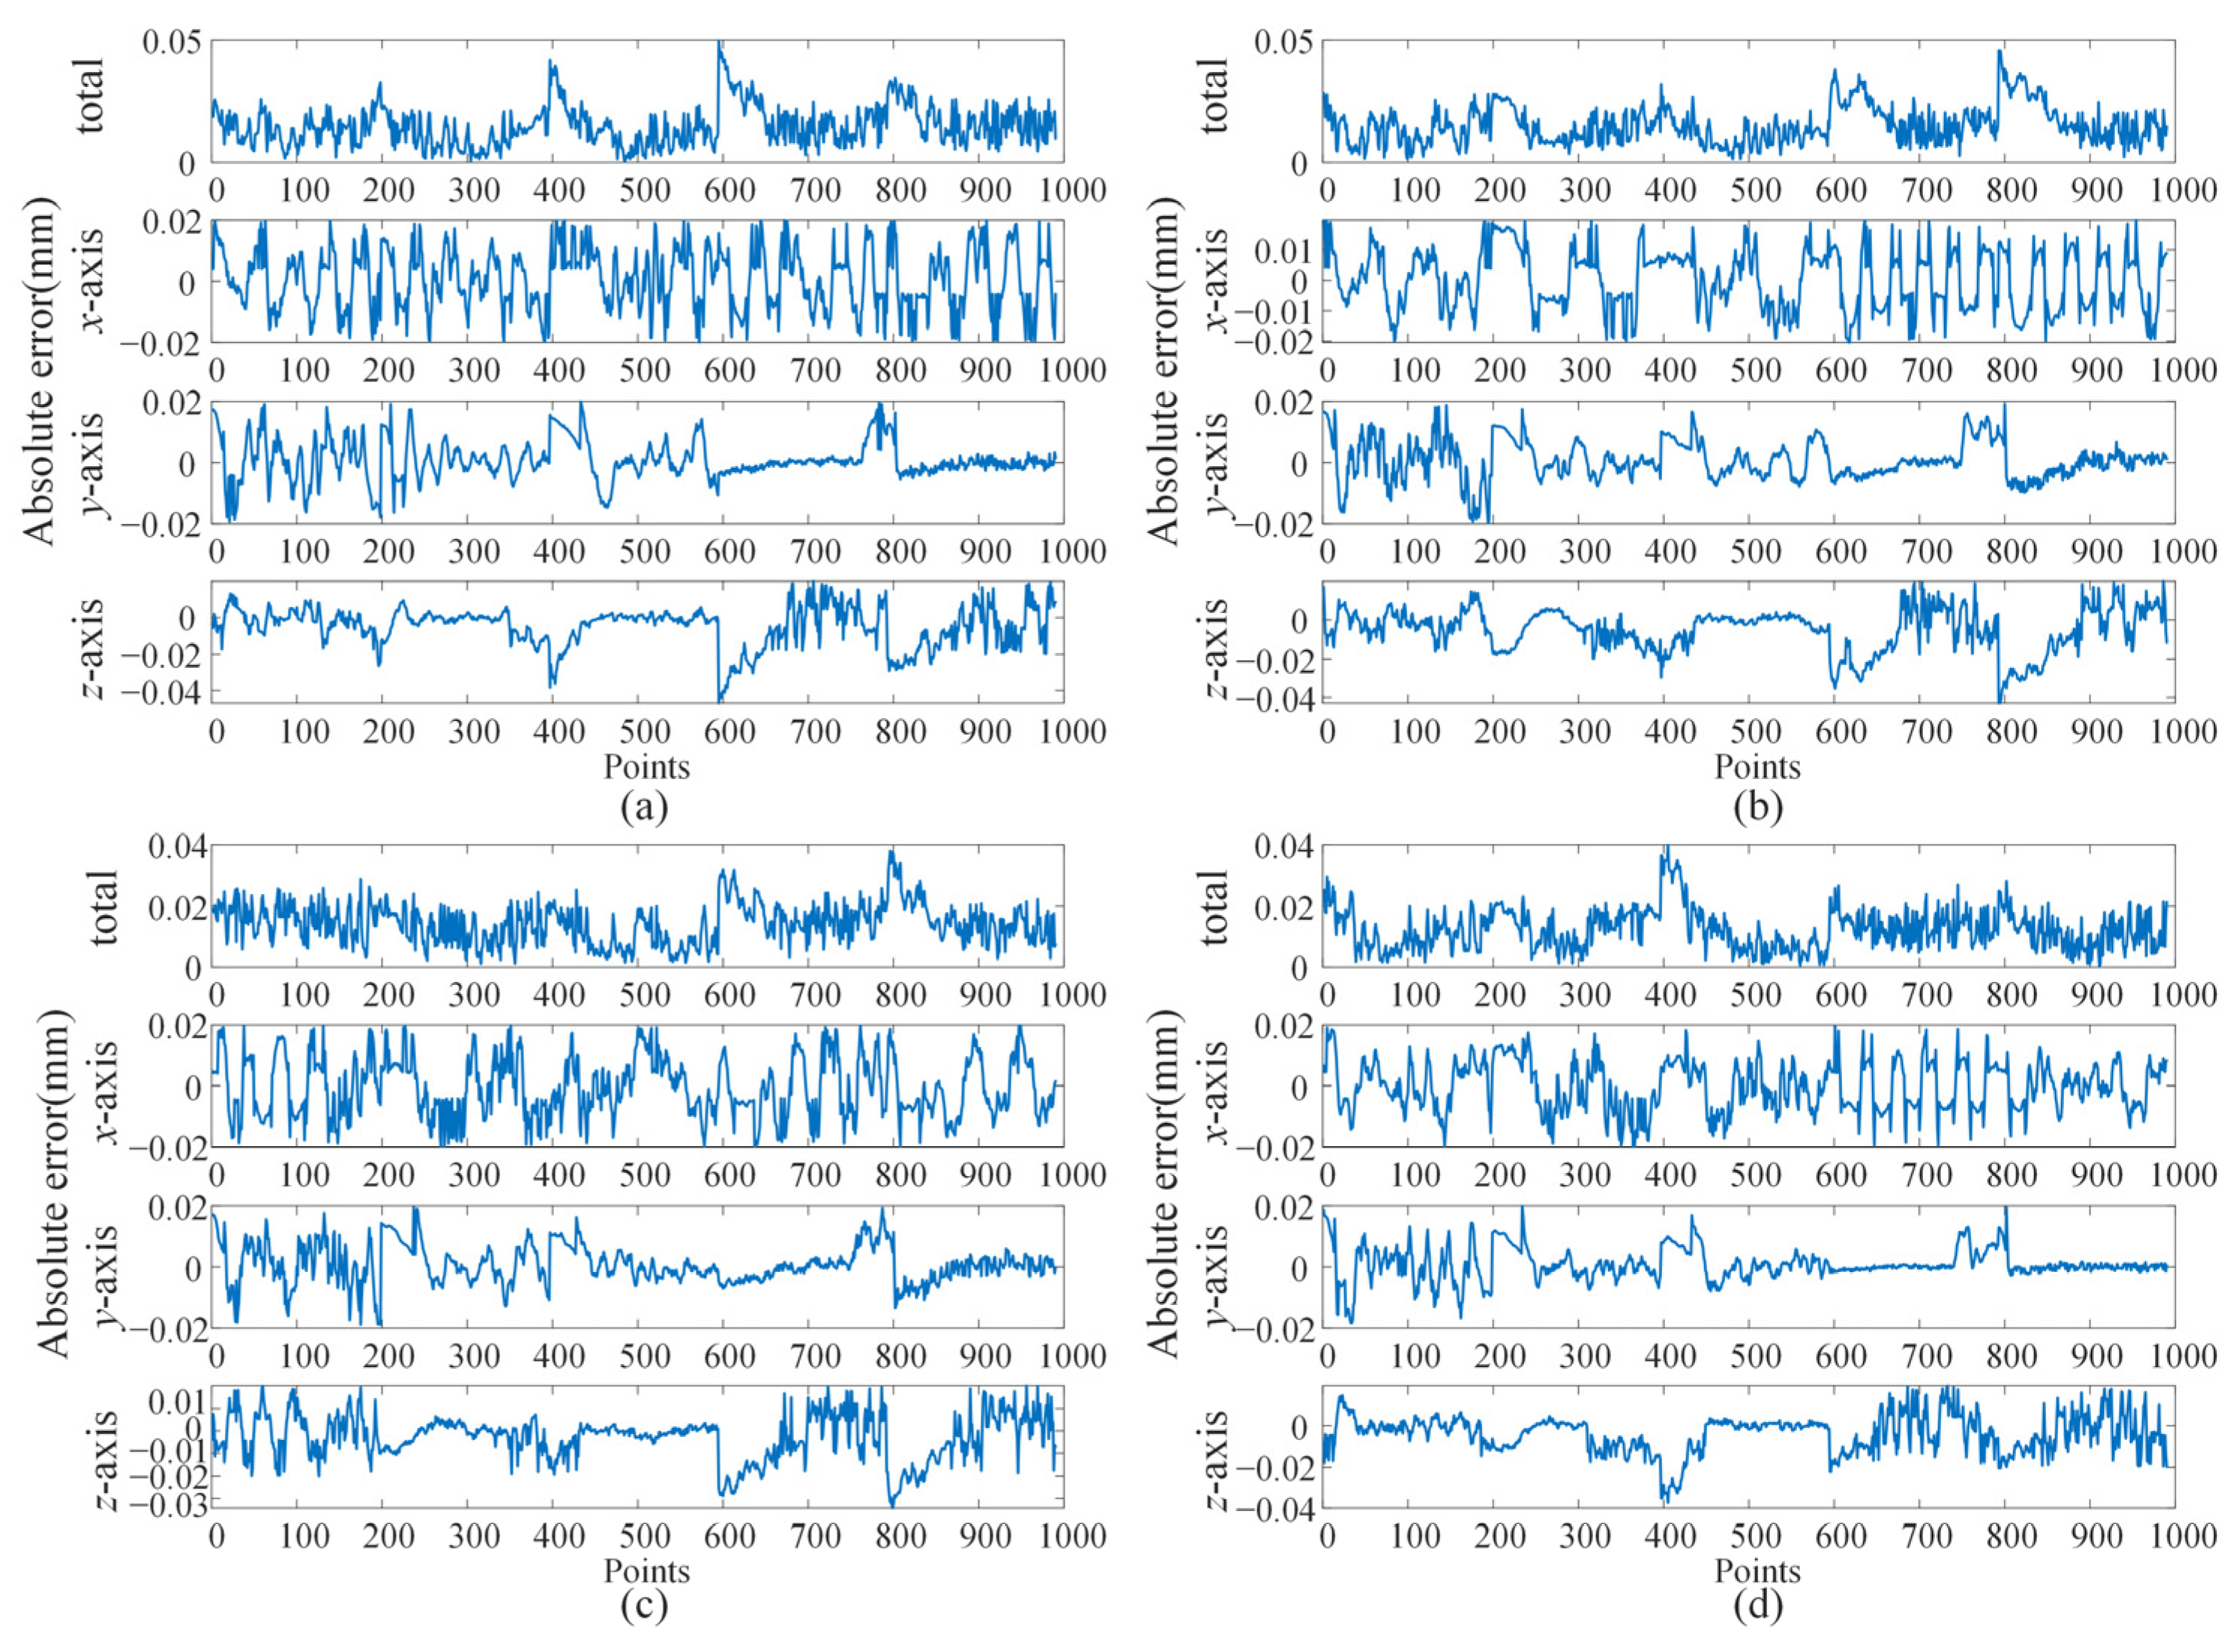

4.3. Break Initiation Experiment in ILM Peeling

| Error | Eye Phantom 1 | Eye Phantom 2 | Eye Phantom 3 | Eye Phantom 4 |

|---|---|---|---|---|

| x/μm | 18.275 | 21.345 | 18.332 | 17.532 |

| y/μm | 9.880 | 10.626 | 10.547 | 8.876 |

| z/μm | 21.920 | 23.598 | 19.249 | 21.823 |

| total/μm | 35.115 | 37.588 | 32.962 | 33.762 |